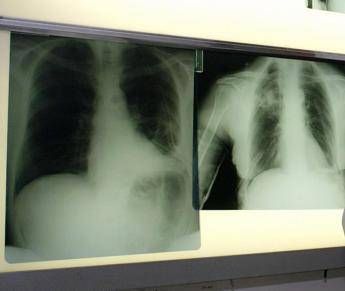

Il tumore al polmone – ricorda l’azienda in una nota – continua a essere una delle neoplasie più diffuse e letali in Italia e nel mondo. Ogni anno, solo in Italia, vengono diagnosticati 44.831 nuovi casi. Circa il 12% riguarda il carcinoma polmonare a piccole cellule, una forma aggressiva e a rapida progressione, per la quale le opzioni terapeutiche sono rimaste a lungo limitate. Negli ultimi anni, tuttavia, i progressi nel trattamento dello Sclc hanno aperto nuove prospettive. Tra questi, un composto sintetico di origine marina – estratto dall’invertebrato Ecteinascidia turbinata – che ha dimostrato risultati promettenti in combinazione come terapia di mantenimento in prima linea per i pazienti con Sclc in stadio esteso (Es-Sclc), una delle forme tumorali più aggressive e con maggiori bisogni clinici insoddisfatti. Come dimostrano i risultati dello studio di fase 3 IMforte, presentato lo scorso giugno all’Asco Annual Meeting 2025 di Chicago, il Congresso dell’American Society of Clinical Oncology, il composto sintetico di origine marina, in combinazione con immunoterapia, riduce del 46% il rischio di progressione della malattia o di morte, con una sopravvivenza mediana globale di 13,2 mesi rispetto ai 10,6 mesi con la sola immunoterapia.

“Il carcinoma polmonare a piccole cellule è una delle forme più aggressive e difficili da trattare di tumore del polmone – spiega Silvia Novello, direttrice della Struttura complessa a direzione universitaria di Oncologia medica dell’Ospedale San Luigi di Orbassano e professoressa ordinaria di Oncologia medica all’Università degli Studi di Torino – Nella maggior parte dei casi, la diagnosi avviene quando la malattia è già in fase avanzata e le opzioni terapeutiche a disposizione sono limitate. I risultati dello studio IMforte rappresentano un’importante novità: la nuova combinazione ha dimostrato un beneficio clinico significativo, con un miglioramento della sopravvivenza globale e della sopravvivenza libera da progressione. Si tratta di dati estremamente incoraggianti – sottolinea – che potrebbero cambiare concretamente l’approccio terapeutico per questi pazienti e aprire una nuova prospettiva di trattamento per una popolazione finora e per troppo tempo priva di alternative efficaci”.